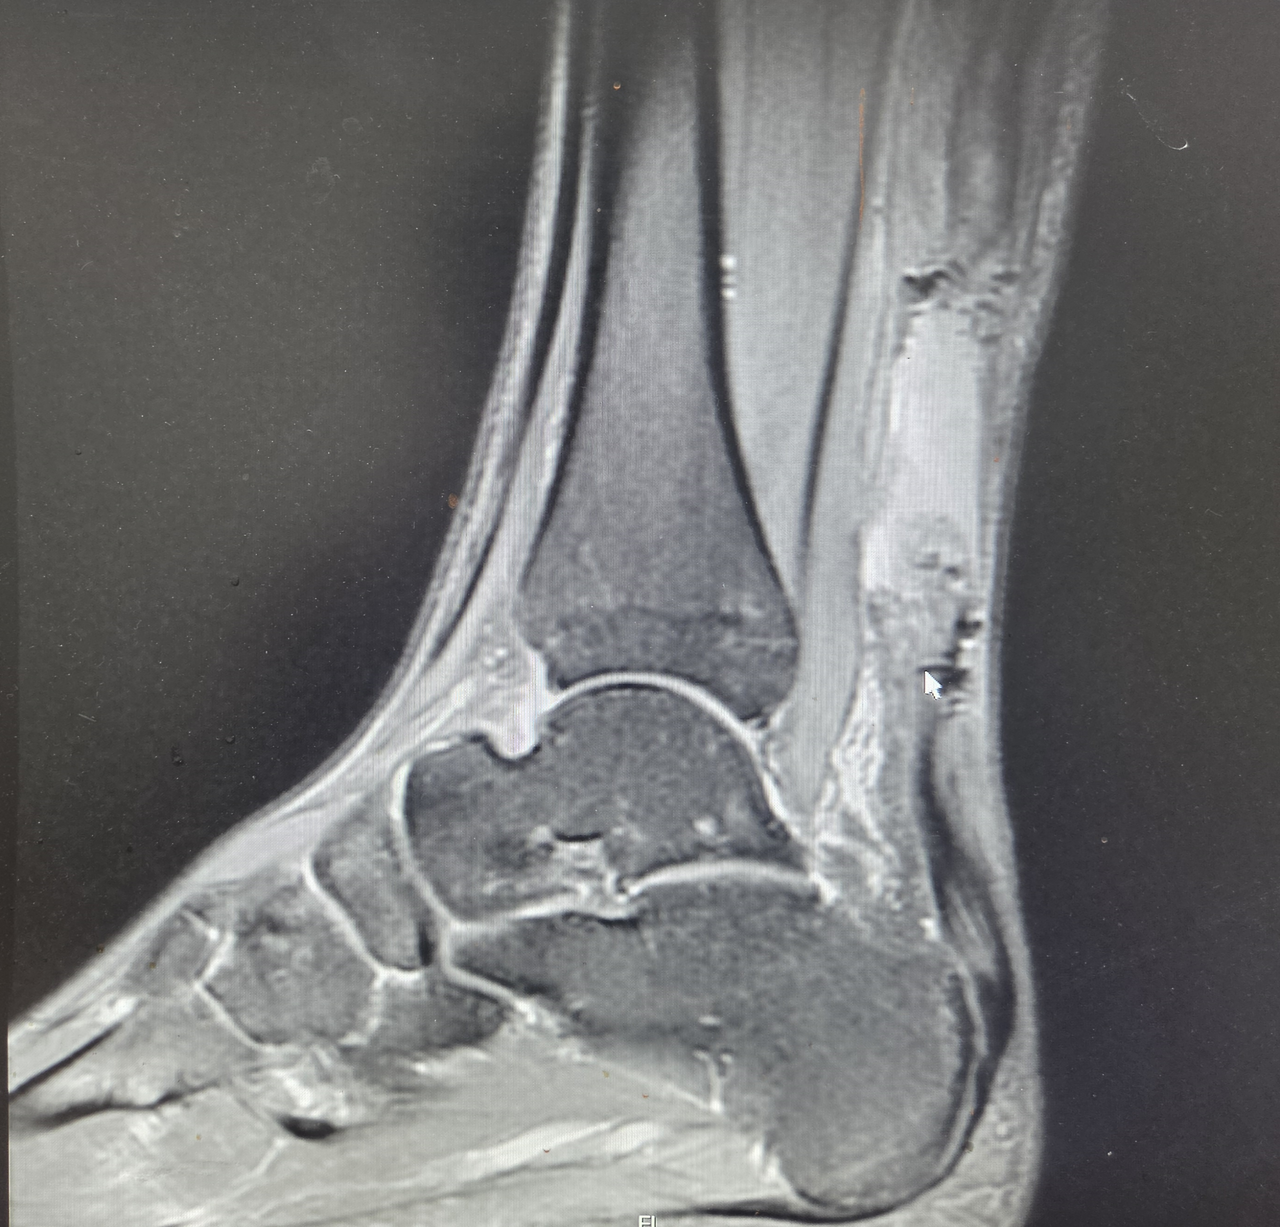

수술은 큰 문제없이 진행되었다. 수술실에서 발목을 강하게 움직여도 봉합 부위가 벌어지지 않는 것을 충분히 확인한 뒤 수술을 마쳤다.

수술 후 3주 동안 흔히 발생할 수 있는 피부 문제도 없이 환자는 비교적 빠르게 회복하고 있었다.

그러던 어느 날 병동에서 연락이 왔다.

환자가 침대에서 내려오는 과정에서 발을 헛디디며 미끄러져 넘어졌다는 것이었다. 넘어지는 순간 발목에서 다시 “뚝” 하는 느낌과 함께 통증이 발생했다고 했다.

환자의 상태를 확인했을 때 재파열이 강하게 의심되는 상황이었다.